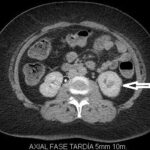

Fase excretora o arterial tardía

Comienza aproximadamente a los 3 minutos posteriores a la inyección del medio de contraste y permite evaluar su excreción por el sistema colector; por lo tanto, es útil para evaluar la relación de la masa con los cálices y la pelvis renal y llegar a una mejor planificación quirúrgica conservadora en un caso dado 3-4 (Fig. 4).